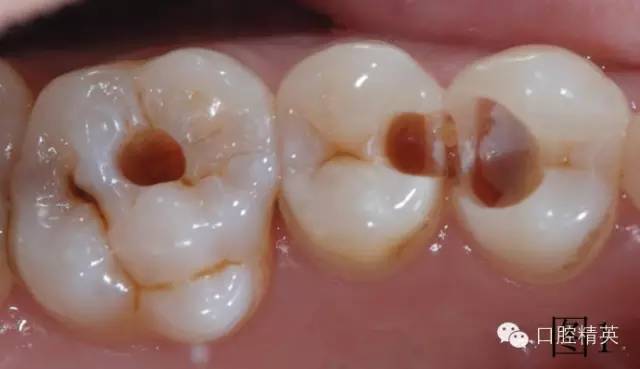

患者自覺左上第一磨牙有洞,檢查發(fā)現小面積充填物脫落,左上第一前磨牙大面積齲壞,離牙神經很近但未漏神經,光固化經氧化鈣墊底,去腐過程中發(fā)現左上第二前磨牙近中隱蔽齲壞,腐質全部去凈,制備窩洞,如圖1。